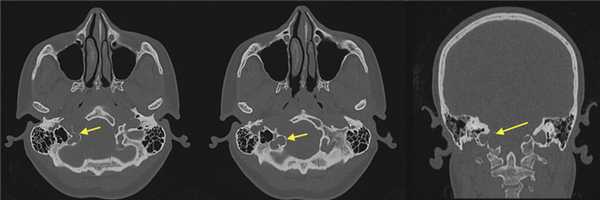

При СКТ головного мозга в костном режиме выявлен расширенный канал подъязычного нерва с деструкцией его стенок. Заднелатеральная стенка практически отсутствовала, вследствие чего полость канала сообщалась с просветом яремного отверстия (рис. 2). Рис. 2. СКТ головного мозга пациентки В. в костном режиме до операции. Определяется деструкция канала подъязычного нерва справа, канал отделен от полости яремного отверстия тонкой костной перегородкой (указано стрелкой).

2. КТ при шванноме подъязычного нерва:

• КТ в костном окне:

о Гладкостенный четко отграниченный расширенный КПН

о Корональная: увеличение размеров, перестройка нижней поверхности яремного бугорка (ниже «орлиного клюва»)

(Слева) При корональной КТ в костном окне наблюдается значительное расширение правого канала подъязычного нерва и эрозия нижней поверхности «орлиного клюва». Сравните наблюдаемую картину с левым каналом подъязычного нерва и яремным бугорком.

(Справа) При МРТ Т1 FS с КУ в корональной проекции у этого же пациента наблюдаются неравномерное контрастирование шванномы, выраженная фестончатость прилегающей затылочной кости и облитерация нормального «орлиного клюва»; те же изменения наблюдаются и на КТ. Слева определяются нормальный канал подъязычного нерва и яремный бугорок.